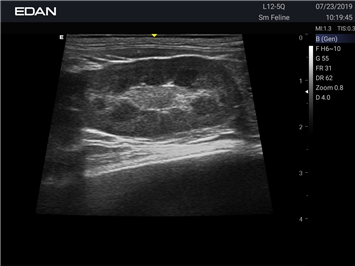

Ветеринарный ультразвук одним нажатием. Система Acclarix AX2 VET разработана с целью обеспечить бескомпромиссную производительность по доступной цене. Наличие уникальных двойных аккумуляторов в легком корпусе массой 4,5 кг из магниевого сплава позволяет системе Acclarix AX2 VET удовлетворять все потребности ветеринарных исследований, сохранив низкую стоимость.

EDAN Acclarix AX2 VET представляет собой специализированную ветеринарную ультразвуковую систему, сочетающую высокую производительность с доступной ценой. Благодаря продуманной конструкции и передовым технологиям, система обеспечивает качественную диагностику животных различных видов.

• Высокое разрешение для детальной диагностики

• Улучшенная визуализация глубоко расположенных органов

B-режим, Двухмерное сканирование:

Да